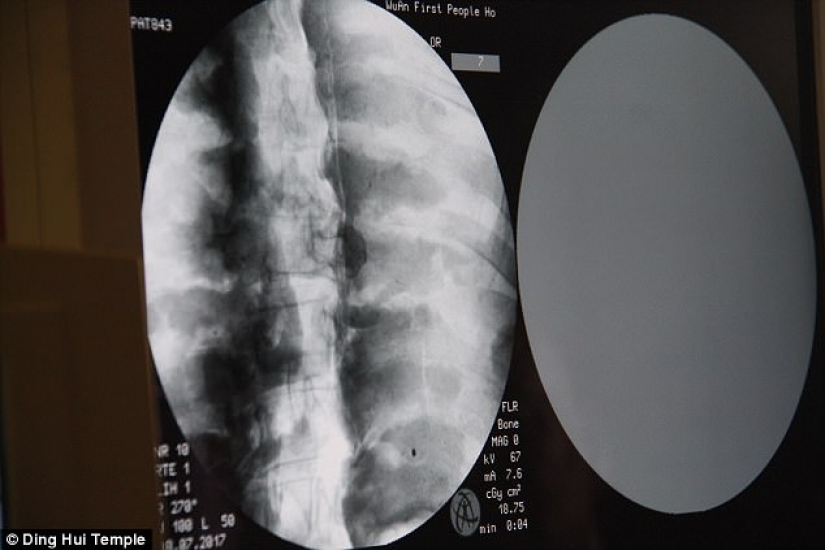

Por Pictolic https://mail.pictolic.com/es/article/una-momia-milenaria-de-un-monje-budista-tiene-un-cerebro-y-un-esqueleto-preservados-en-perfecto-estado.htmlEl cuerpo momificado de un monje budista de mil años todavía tiene los huesos y el cerebro intactos. Esto fue revelado por una tomografía computarizada.

La tomografía computarizada se realizó el 8 de julio. La gente se sorprendió cuando los médicos dijeron que el esqueleto y el cerebro de Ci Xian estaban en perfectas condiciones. "Podemos ver que sus huesos están tan sanos como los de una persona normal: la mandíbula superior, los dientes superiores, las costillas, la columna vertebral y todas las articulaciones están perfectamente conservadas. Esto es increíble", dijo el Dr. Wu Yongqing.